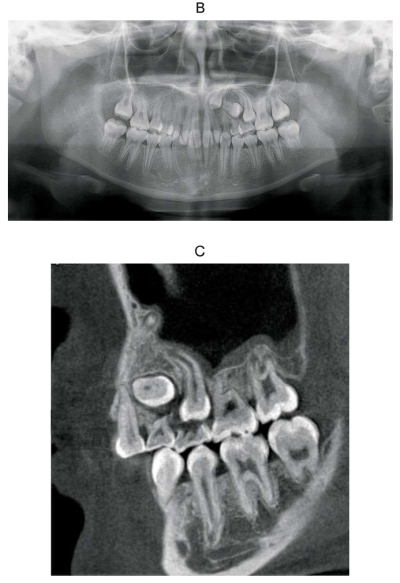

13 歳の女子。歯並びが悪いことを主訴として来院した。初診時の口腔内写真、エックス線画像及び歯科用コーンビーム CTを別に示す。正しい所見はどれか。2つ選べ。

a. 1⏊1の低位

b. ⎿3の遠心傾斜

c. ⎿4の水平埋伏

d. ⎿5の歯根彎曲

e. ⎿7の萌出遅延